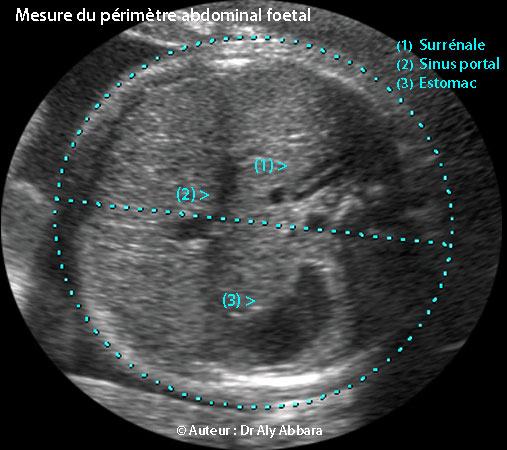

- أنه مقطعٌ مستعرضٌ لبطن الجنين يمر في كلٍ من المعدة، جيب الوريد البابي والغدة الكظرية ؛ على هذا المقطع يجب ألا ترى الكُلى ولا أي جزءٍ من الرئة.

- أهم نقاط العلام في هذا المقطع هما طبعاً الغدة الكظرية و جيب الوريد البابي، أما المعدة فيمكن عدم رؤيتها مثلا إذا كان الجنين قد أفرغها لتوه, أو في حالات رَتَق المريء.

- محيط البطن الجنيني يأخذ شكلاً إهليليجياً ماراً في سطح التماس ما بين سطح جلد البطن والسائل الأمنيوسي

- Il s'agit d'une coupe transversale de l'abdomen fœtal passant par trois points de repère qui sont :

- l'estomac ;

- le sinus portal (l'angle presque droit que dessine la veine ombilicale) ;

- la surrénale.

- Les deux principaux repères sont le sinus portal et la surrénale, car il est possible de ne pas voir l'estomac s'il vient de se vider, ou en cas d'atrésie de l'œsophage.

- Dans cette coupe il ne faut pas voir, ni les reins ni les poumons.

- Le périmètre (ou la circonférence) abdominal fœtal dessine une ellipse passant par l'interface entre la surface de la peau de l'abdomen et le liquide amniotique.